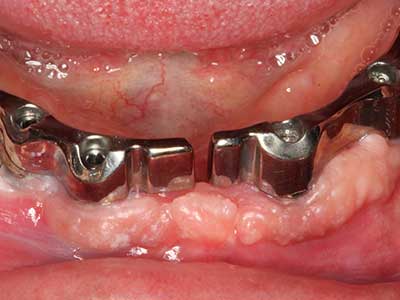

Fig. 13: l'irrigazione adeguata con l'osso residuo largo 4 mm è essenziale durante l'incisione ossea di questo paziente di 52 anni.

Fig. 14: posizionamento di quattro impianti RSX conici (BEGO Implant Systems, Brema).

Fig. 15: la radiografia dopo un follow up di un anno mostra condizioni stabili a livello osseo.

Fig. 16: anche le condizioni intra-orali sono stabili, con l'incorporazione degli impianti nella gengiva cheratinizzata.